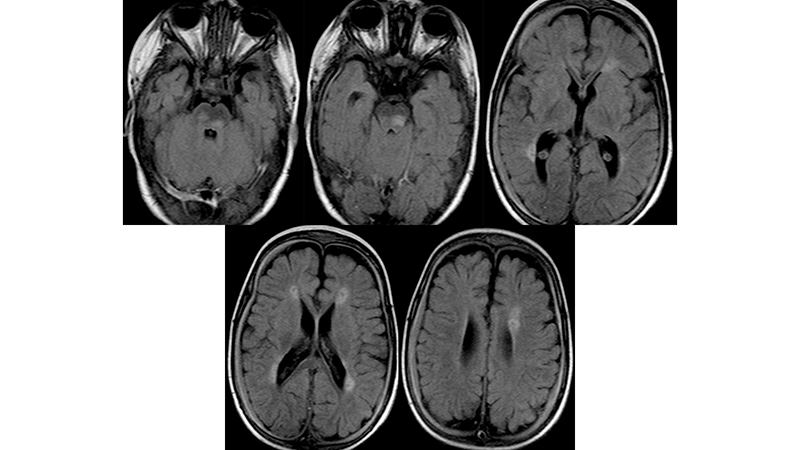

- Στην μαγνητική τομογραφία βλέπουμε μικροισχαιμικές αλλοιώσεις στο εγκεφαλικό στέλεχος και υποεπενδυματικά,

- και υποσκληρίδια αιματώματα αμφοτερόπλευρα, κυρίως δεξιά.

- Πρόσφατη μαγνητική τομογραφία δείχνει αναστροφή των ισχαιμικών αλλοιώσεων του εγκεφαλικού στελέχους, αποκατάσταση του κοιλιακού συστήματος με ήπια υποεπενδυματική και φοιώδη ατροφία και πλήρη εξάλειψη των υποσκληριδίων συλλογών.